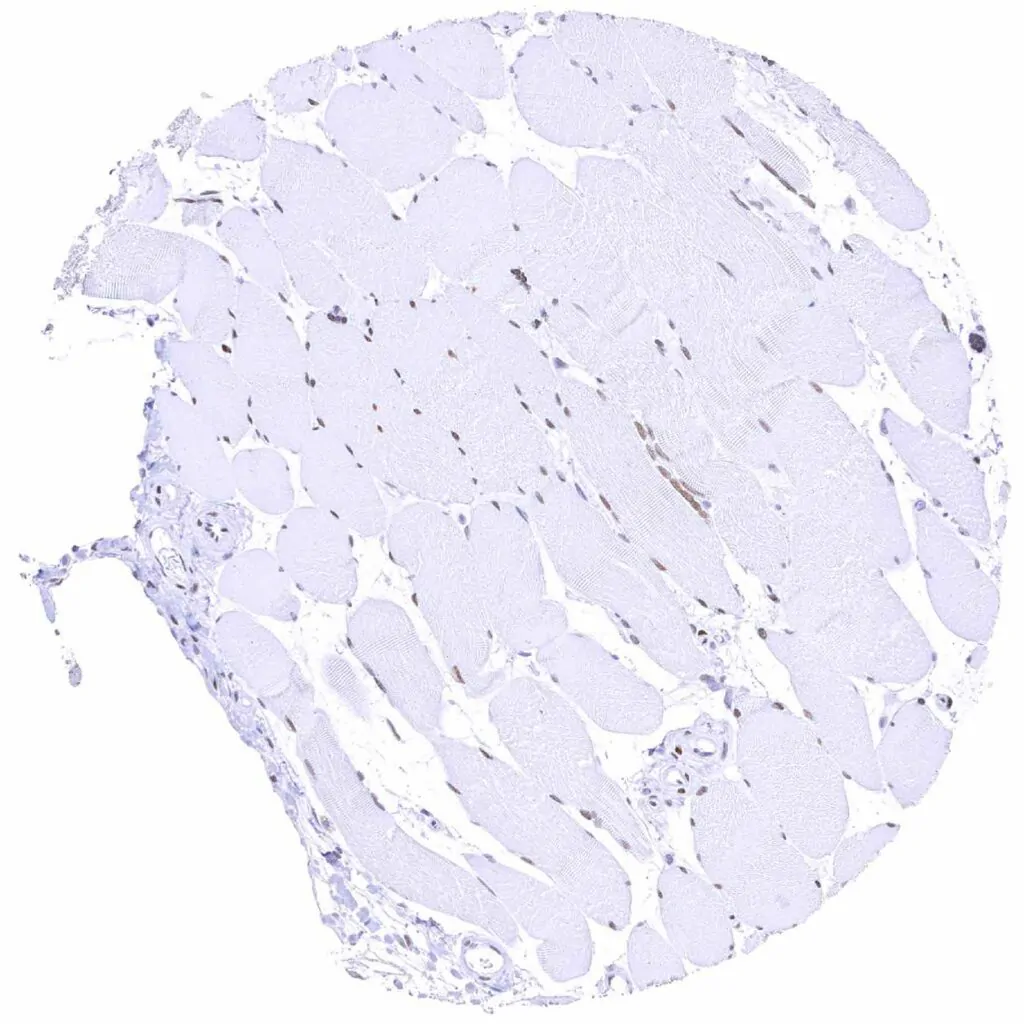

Heart muscle